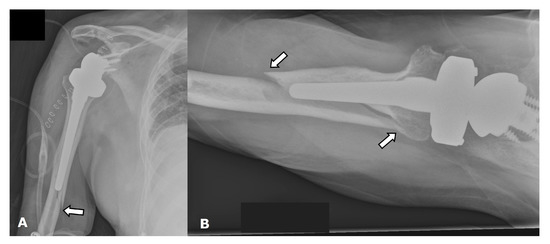

4.2.2. Stress Shielding and Fractures

5.3. Revision Shoulder Arthroplasty